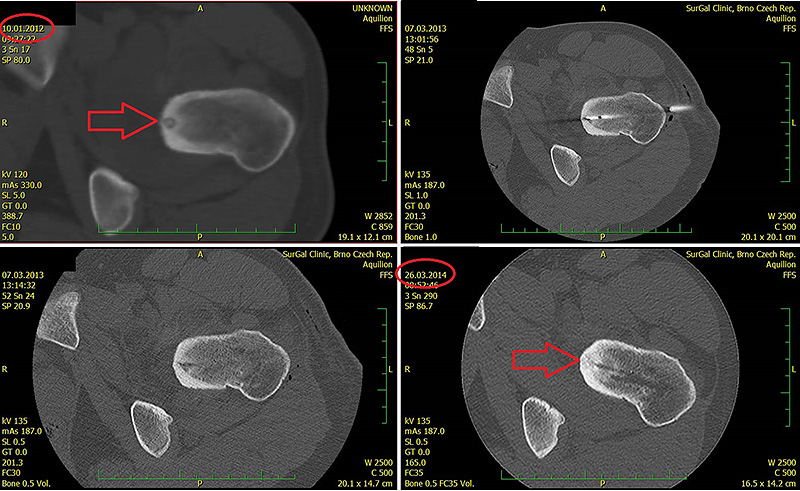

Obr. 3 Radiofrekvenční ablace osteoidního osteomu na CT zákrokovém sále

Obr. 4 Kontrola po roce, patrná je sklerotizace nidu osteoidního osteomu

Obr. 6. RFA osteoidního osteomu levé kyčle a CT kontrola po roce